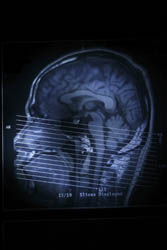

La tomografia computerizzata (CT), la risonanza magnetica (MRI) e la tomografia a emissione del positrone (PET) sono tecniche di imaging che forniscono dati anatomici e fisiologici completi di estrema importanza per guidare la diagnosi e la terapia nella pratica clinica. Questi metodi però non sono in grado di valutare i parametri sistemici come il battito cardiaco o la pressione arteriosa e non si possono applicare accanto al letto. L'elettroencefalogramma (EEG) costituisce una tecnica di vecchia data che può monitorare il cervello continuamente e in maniera non invasiva. Il consorzio NEUROPT ("Non-invasive imaging of brain function and disease by pulsed near infrared light"), finanziato dall'UE, desiderava generare uno strumento clinico per il monitoraggio continuo dei parametri emodinamici dell'ossigenazione e la perfusione cerebrale. Questo strumento dovrebbe complementare anche i metodi MRI/CT/PET e allo stesso tempo essere compatibile con le tecniche esistenti di neuro-monitoraggio (EEG, Doppler ultrasuono). Per ottenere ciò, i partner hanno dovuto migliorare la risoluzione spaziale delle attuali tecniche di imaging, eliminare i manufatti e permettere la quantificazione assoluta dei parametri fisiologici. A questo fine, hanno impiegato tecniche a tempo risolto che offrono una maggiore sensibilità rispetto alla maggior parte dei metodi ottici e distinguono tra i tessuti di superficie (per es. la pelle e il cranio) e il tessuto cerebrale. Sono stati costruiti nuovi dispositivi fotonici e prototipi da usare in condizioni cliniche, compreso un elmetto specializzato per attaccare le fibre ottiche alla testa. Attraverso lo sviluppo del software, i ricercatori hanno potuto anche analizzare le misurazioni a tempo risolto sulla testa e calcolare le concentrazioni di ossiemoglobina e deossiemoglobina. Inoltre, i ricercatori di NEUROPT hanno lavorato sulla modellazione realistica e il calcolo, con particolare attenzione al miglioramento della propagazione della luce nella testa umana. La fattibilità di questo approccio combinatorio è stata testata in studi separati visivi e motori in soggetti sani. È stato poi applicato con successo per effettuare misurazioni in pazienti con gravi condizioni neurologiche, epilessia fotosensibile o ictus. Data la natura non invasiva dell'approccio di NEUROPT e la possibilità di usarlo accanto al letto, esso dovrebbe facilitare la diagnosi della menomazione cerebrale funzionale e monitorarne i progressi. Di conseguenza, dovrebbe migliorare la prognosi di pazienti affetti da gravi malattie neurologiche e si potrebbe applicare anche per l'imaging del cervello dei bambini piccoli.